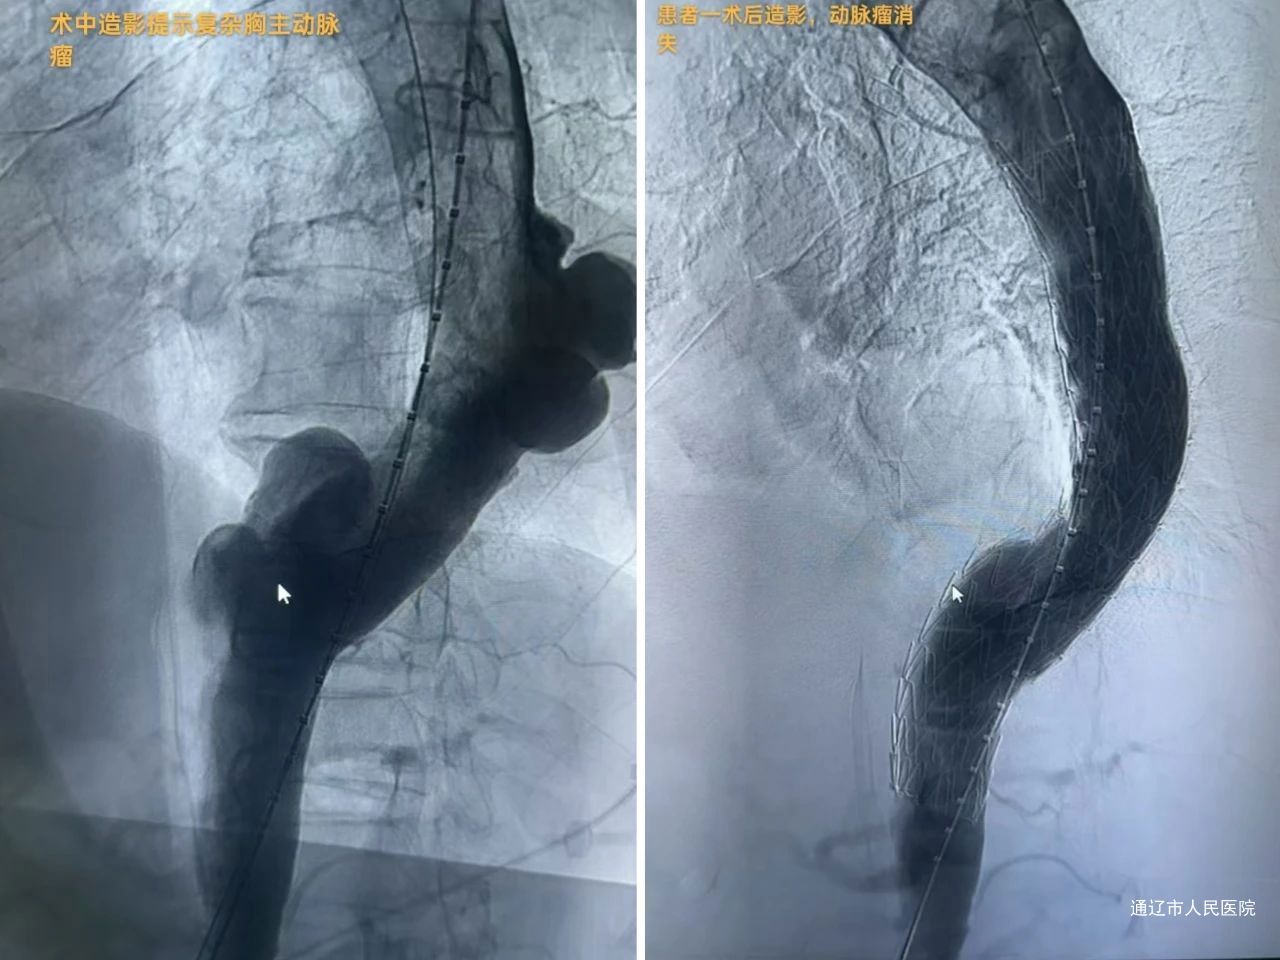

主动脉瘤与主动脉夹层属于致死率极高危重症,传统开放手术创伤大、风险高,尤其对于高龄、基础疾病多、解剖结构复杂的患者,治疗难度极大。血管肿瘤介入科团队依托先进的数字减影血管造影(DSA)设备,结合个体化三维手术规划,通过微创腔内修复术(EVAR/TEVAR),成功为多名高危患者解除生命威胁,展现了介入技术的突破性优势。

复杂胸主动脉瘤患者王某,因肺功能差被多家医院判定为开放手术禁忌症,血管肿瘤介入科团队仅通过双侧股动脉穿刺预制缝合器技术完成“胸主动脉瘤腔内修复术”,术后次日即可下地正常活动;腹主动脉夹层患者李某某发病时出现下肢缺血、尿量减少等器官灌注不足症状,经手术重建主动脉真腔后肢体温暖、尿量恢复。“没想到不用开刀就能治好这么严重的病,是介入技术给了我第二次生命!”两位患者康复出院时,难掩感激之情。